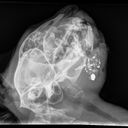

Hi my name is Anita and this is my cat Thomas J aka Tommy. Back in 2021 I took in a stray cat after someone had shot him in the face. After we found him laying there and barely clinging on to life we rushed him to the vet. The gunshot wound had shattered his lower jaw bone and he had to be confined and treated for the infection. Although the vet told us that there was no way they could remove the smaller scattered pieces of shrapnel the larger piece of bullet did come out of the exit wound. I have loved and cared for Tommy and he has become my dearest friend and my family. Tommy has thrived with the gunshot wound until recently. I had to take him back to the vet and where is jawbone didn't grow back properly it has caused his mouth to be a little crooked and some of his teeth have protruded out of his mouth and have become infected. The vet said he needs to surgically extract his infected teeth. I wouldn't normally ask of something like this, but these past few months have been really hard financially and I desperately need help to get my dearest friend feeling back to his sweet self and feeling better. I sincerely thank you all for taking the time to listen to my story and God bless you all. You can make donations to me or directly to logan county animal clinic [phone redacted]. My name is Anita jo etheridge and cat name is Thomas J Aka Tommy. Thank you all.